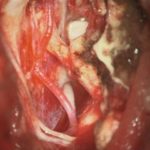

703

'25年12月

50代

先端巨大症

頭蓋内腫瘍摘出術

No.’25_105 摘出 前

No.’25_105  摘出 中

No.’25_105 摘出 後